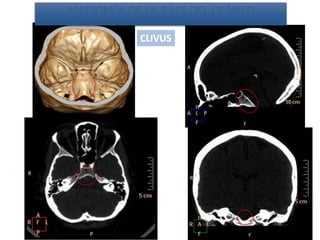

ANATOMÍA DE LA BASE DEL CRÁNEO

CLIVUS